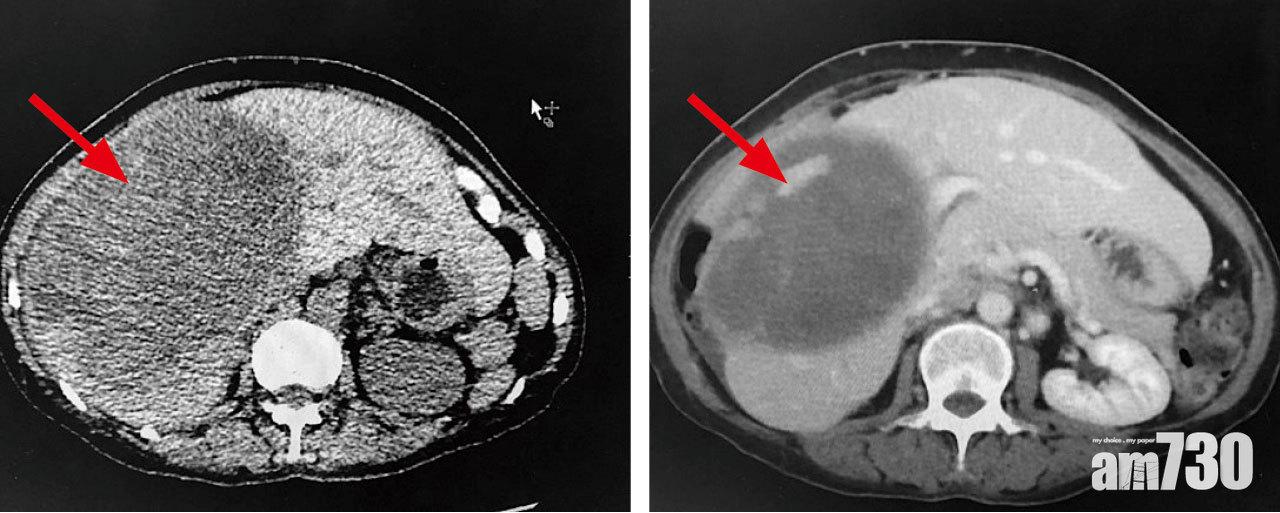

服用新藥後3個月,姚女士的腫瘤直徑由19厘米(左)縮至14.5厘米(右)。

肝功能改善

60歲患者姚女士分享抗癌經歷,「去年3、4月持續上腹痛,誤診以為是胃問題,到11月獲悉患上肝癌第四期,腫瘤已達19厘米,癌細胞又擴散至肺部,公立醫生建議只作紓緩治療,並預告壽命只剩3個月。」同月她從私家醫生獲悉新標靶藥樂伐替尼,用藥一個月病情即有好轉,「甲胎蛋白水平由760下降至14,3個月後腫瘤縮小至14.5厘米,癌指數下降,肝功能也有改善。」該藥今年獲醫管局納入自費藥物名冊,「每月兩萬多元藥費,現幾乎耗盡積蓄。」她希望政府盡快將更多藥物納入安全網,令更多患者能得到援助,專心抗癌。